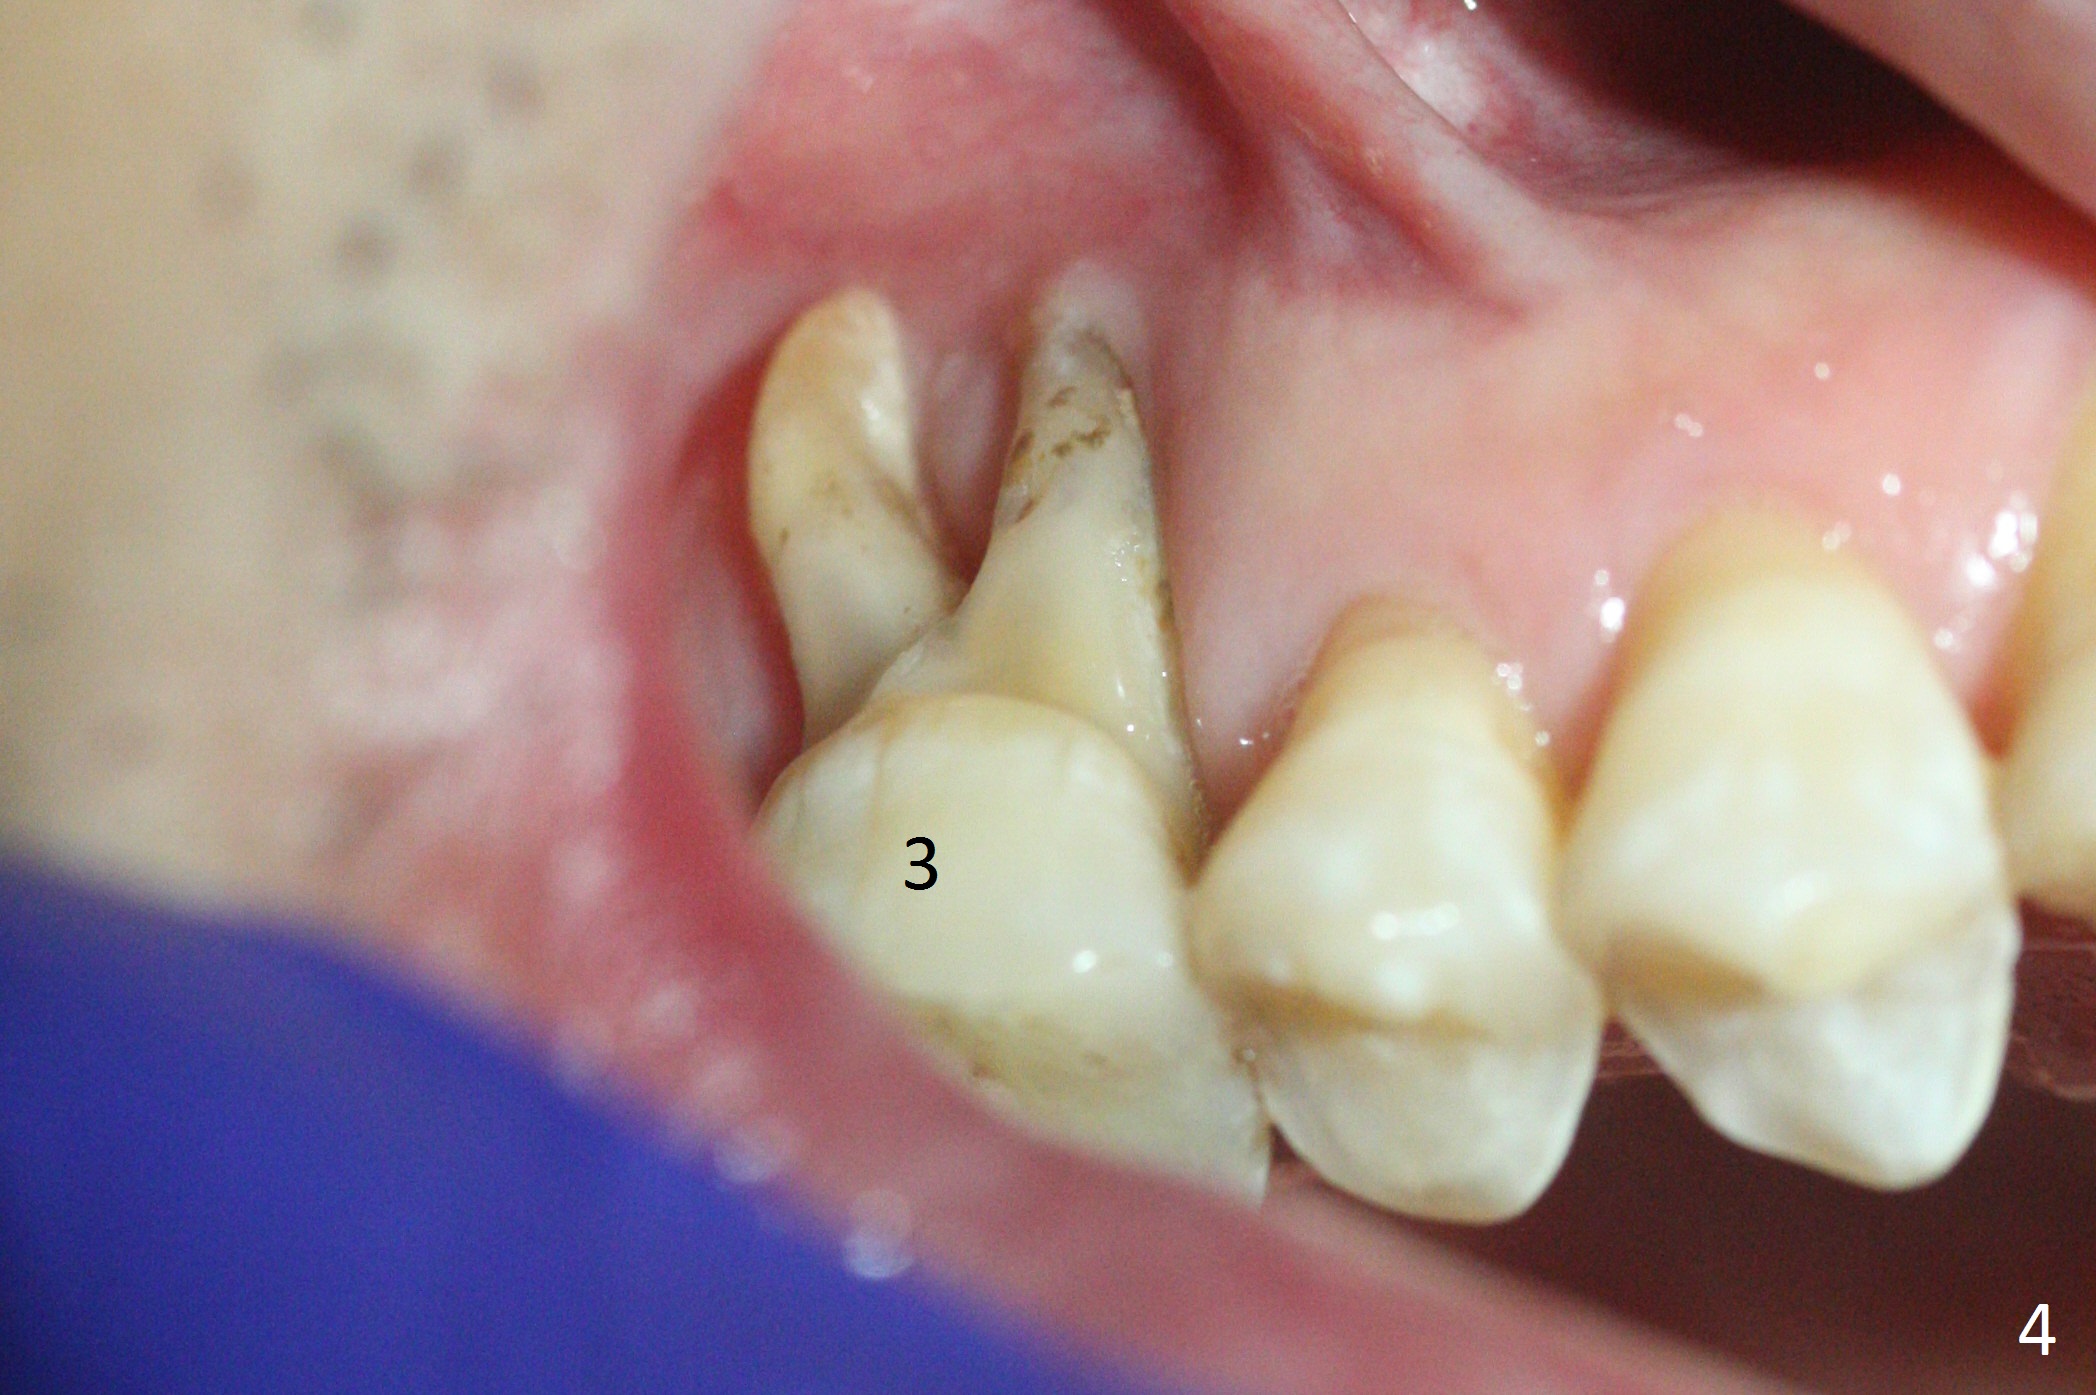

When the crown at #19 is cemented, the tooth #3 is found to have severe buccal recession (Fig.4). A 5.3x10 mm implant is not only placed deep, but also palatal (Fig.5, Clindamycin). An abutment will be selected with the longest cuff (6 mm (pink)). To make the palatal gingival margin recede, the coronal palatal bone (<) will be broken and pushed to the palatal socket.